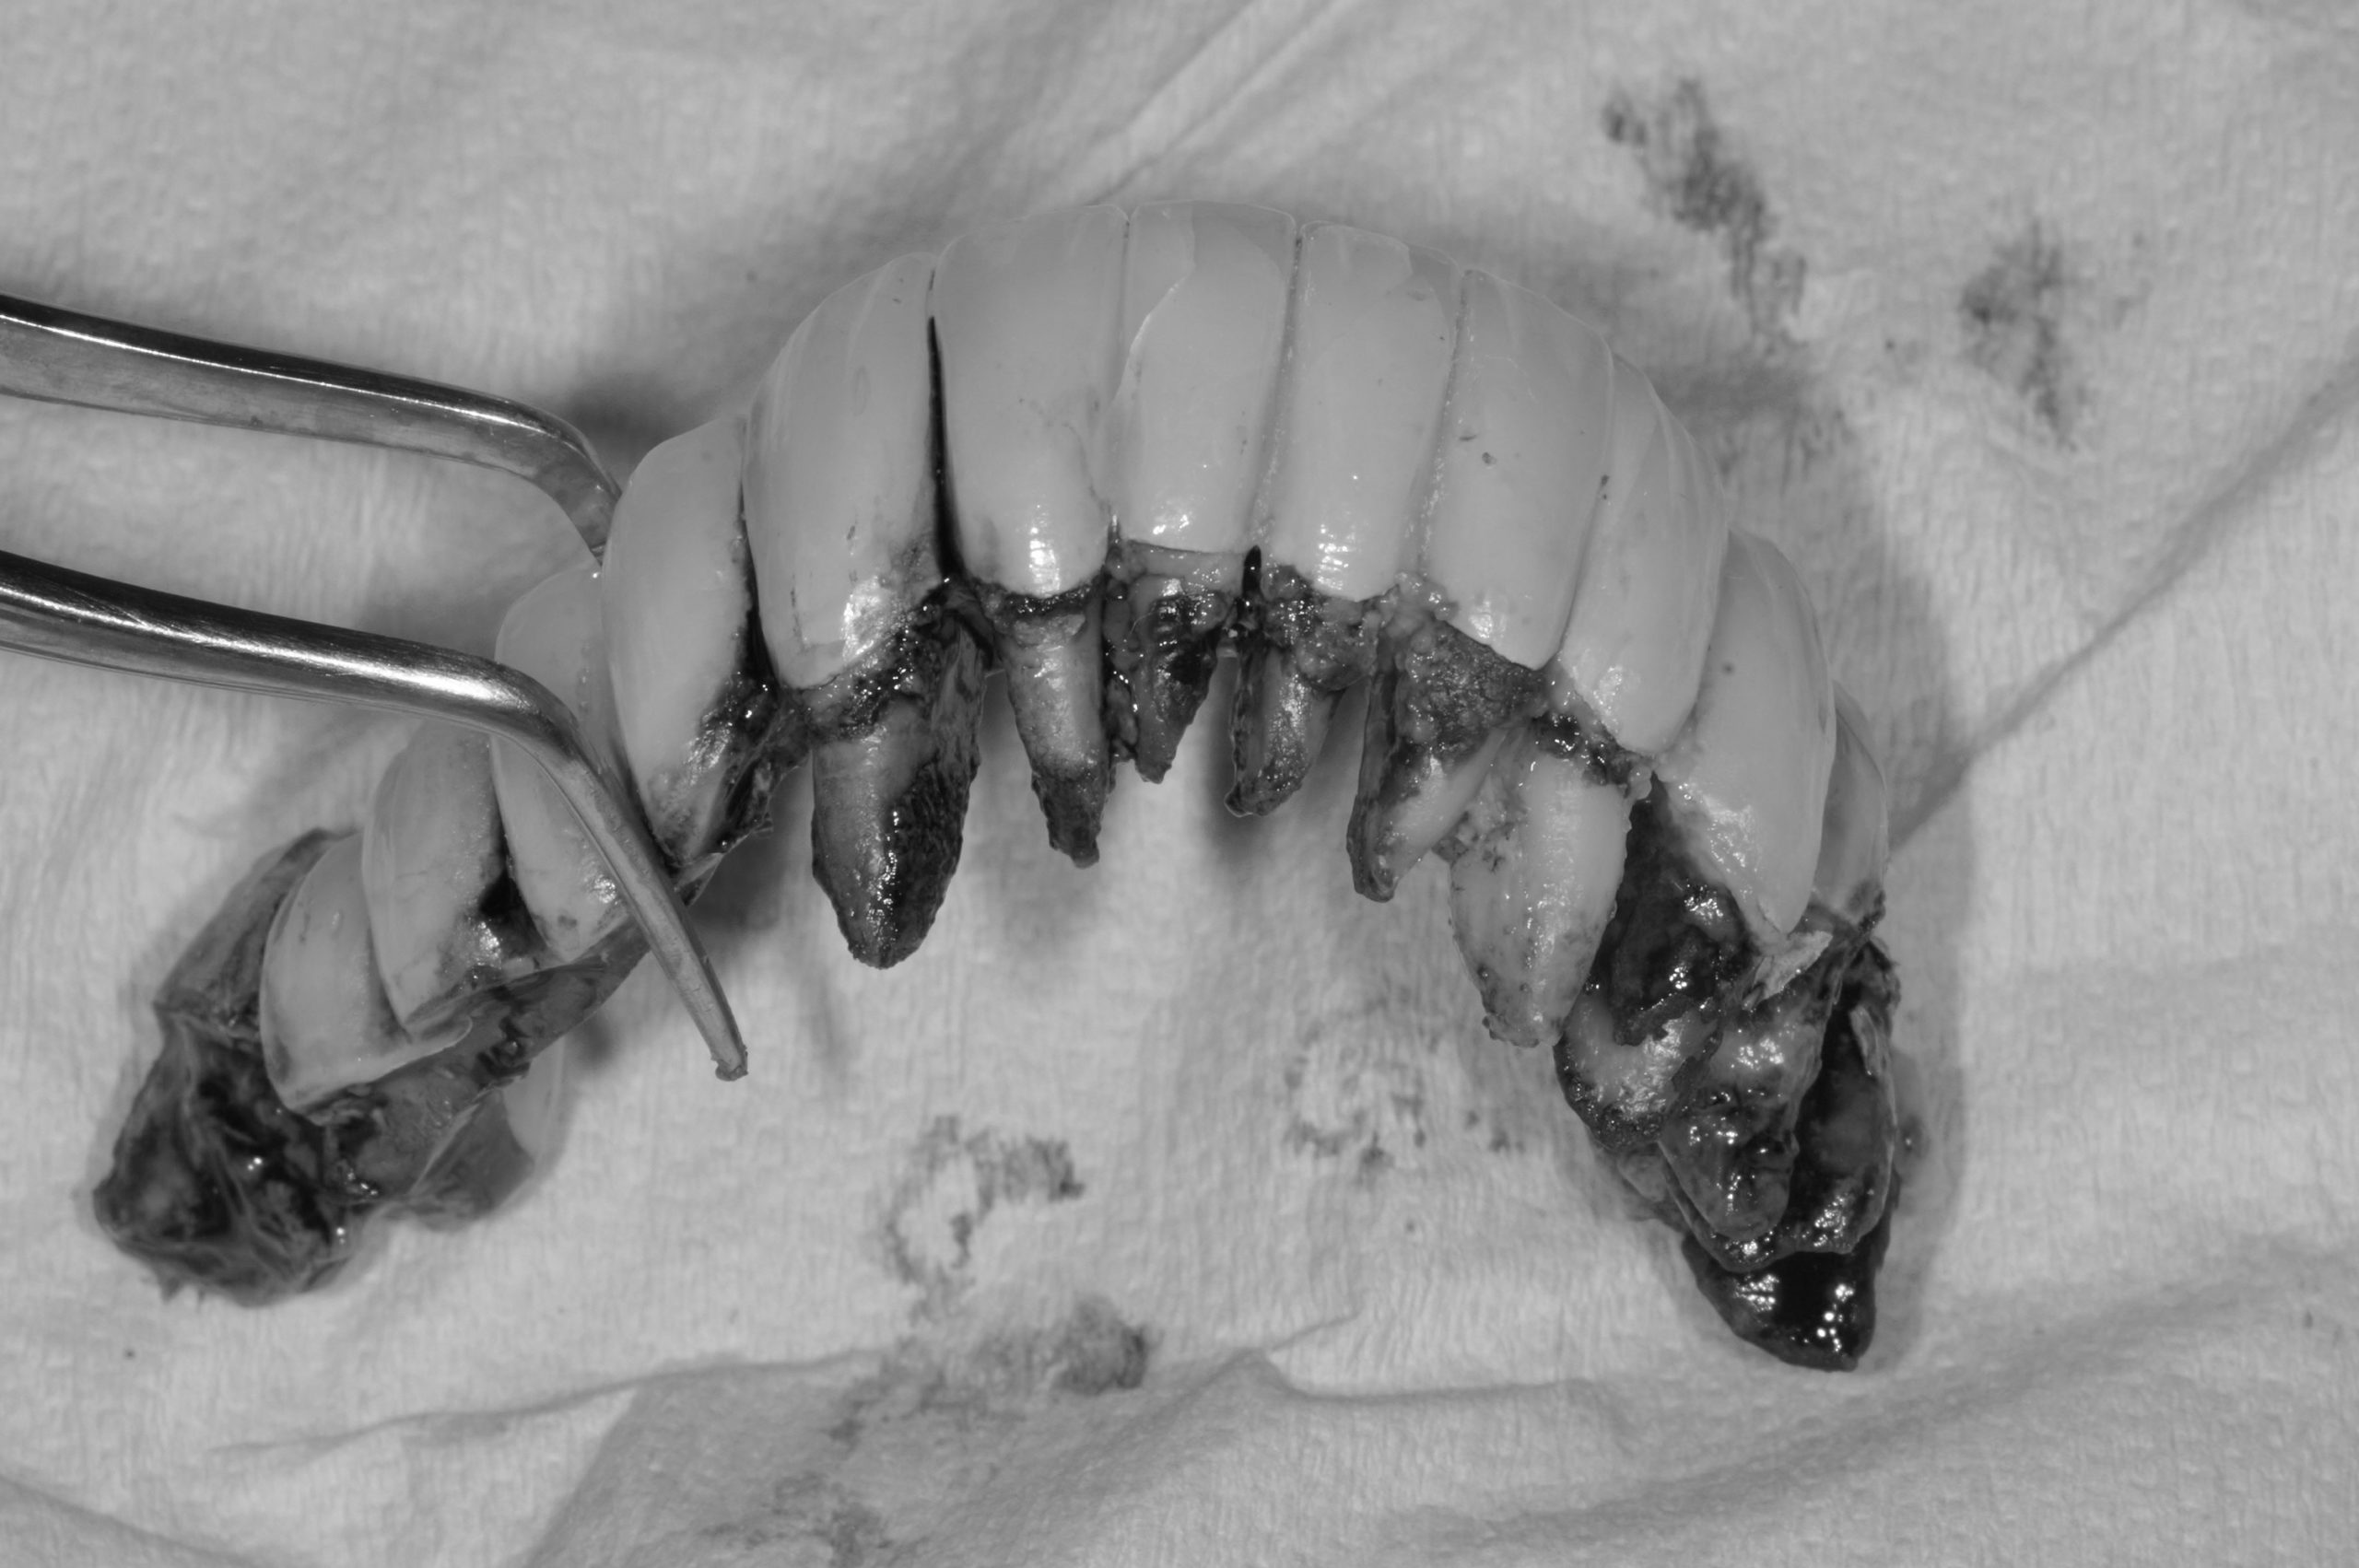

殊不知,台灣首創「導航全口植牙教育中心」就在新竹,有亞洲規格最多台的導航訓練設備。而陳女士很幸運地來到此地,於是接受了複雜程度最高的四隻顴骨植體(zygoma implant)導航手術,配合鎮靜舒眠麻醉下,當日陳女士終於有一副好用的固定假牙吃東西了,兩個女兒也很開心見到母親重拾笑容。